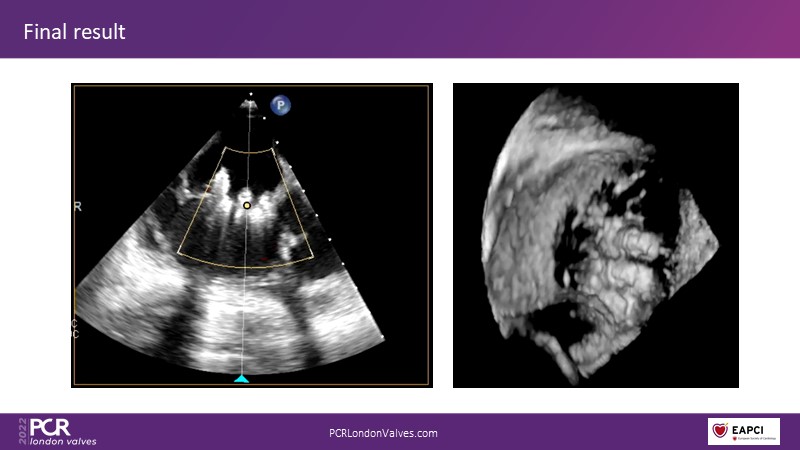

Join this panel of experienced physicians to learn more about the novel PASCAL Precision system and to discuss implant selection and clinical data. Finally, participate in a recorded case demonstrating the use of the PASCAL Precision system for the treatment of mitral regurgitation.

- To attend clinical evidence and case-based discussions that will highlight key differentiators of the novel PASCAL Precision system and its clinical impact

- To participate in a recorded case demonstration using the novel PASCAL Precision system for the treatment of mitral regurgitation